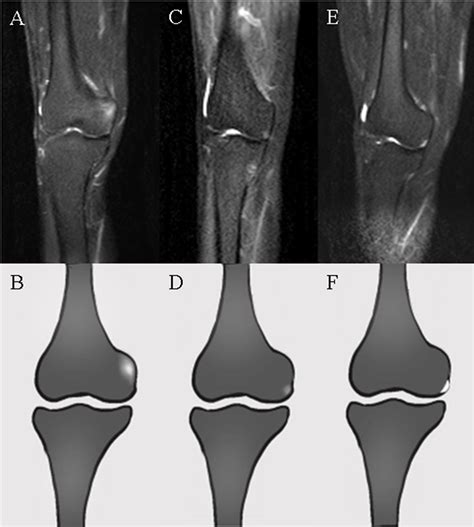

Bio-engineered Grafts Will Soon Replace A Damaged Tibial Band